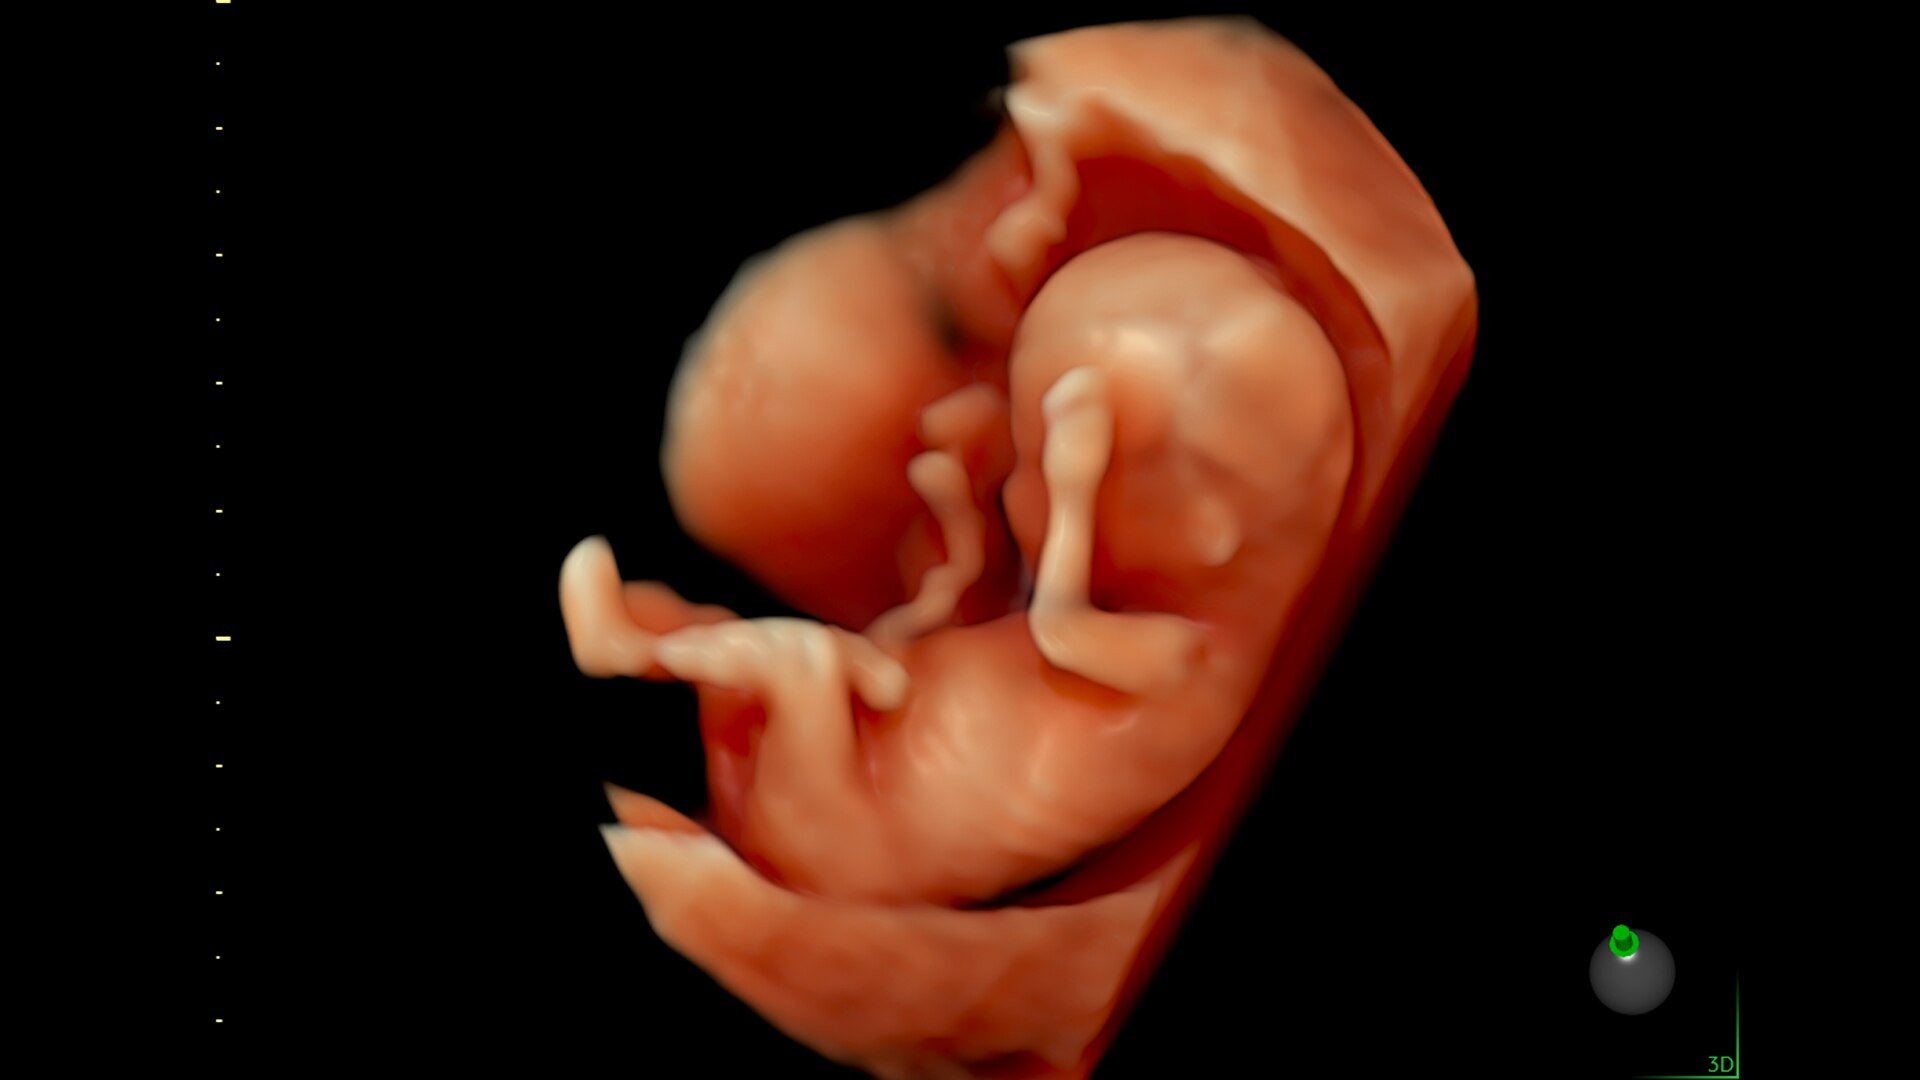

Voluson Signature20

The Voluson Signature 20 is a top performer. Powered by a progressive, highly flexible system architecture and coupled with Voluson’s advanced transducer technology migrated from our premium Expert series platform, take a big leap in image quality. With a new level of depth and clarity, accelerate your diagnostic capabilities so you can always deliver your most confident care.

Advanced beamforming capabilities work in harmony with expert-level probes to deliver faster processing speeds and frame rates for enhanced detail and contrast resolution, greater color quality and sensitivity, and exceptional 3D/4D.